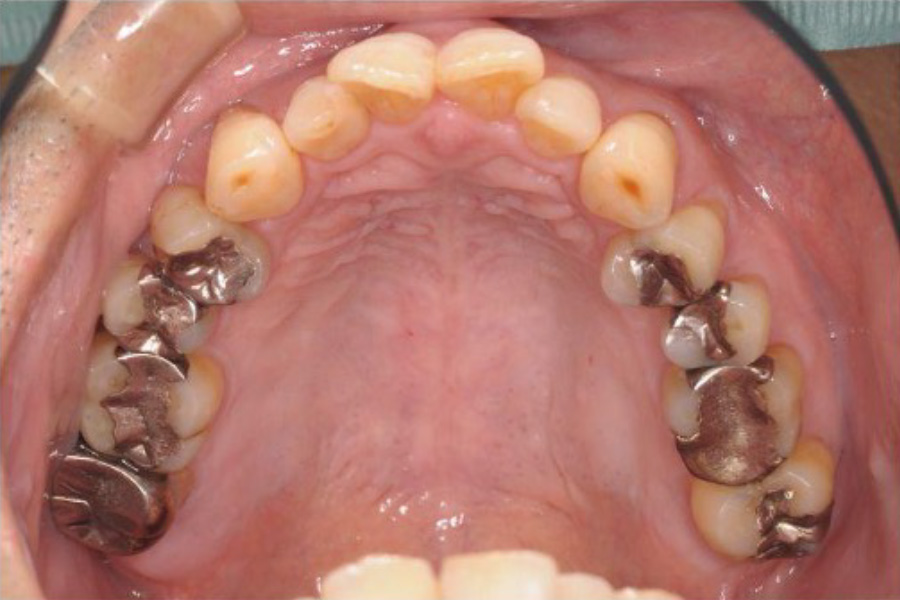

治療後

| 期間 | 5年 (実質2年、本人都合により3年中断、メインテナンス予防1年目) |

| 費用 | 434,500円 (保険治療、矯正治療) |

| 治療内容 | 全顎治療:歯周病治療、抜歯、根管治療、 咬合治療・矯正治療、フルメタルクラウン(保険) |